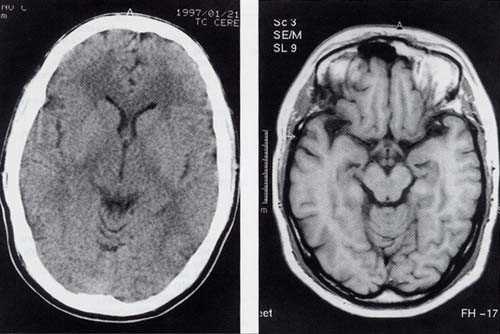

Магнитно-резонансная томография (МРТ) предоставляет более детальную информацию о состоянии межпозвоночных дисков и окружающих тканях, что делает её предпочтительной для диагностики сложных случаев. МРТ не использует ионизирующее излучение, что также является важным фактором для многих пациентов.

Компьютерная томография (КТ) часто применяется в экстренных ситуациях, когда необходимо быстро получить информацию о состоянии пациента. КТ позволяет точно визуализировать костные структуры и выявить возможные осложнения. Однако, как и в случае с МРТ, КТ сопряжена с воздействием радиации.

Вопрос выбора метода визуализации грыжи вызывает много обсуждений среди специалистов и пациентов. Ультразвуковое исследование (УЗИ) часто хвалят за доступность и отсутствие радиации, что делает его идеальным для первичной диагностики, особенно у детей. Однако его ограниченная способность визуализировать глубокие структуры может быть недостатком. Магнитно-резонансная томография (МРТ) предоставляет более детализированные изображения мягких тканей и позволяет лучше оценить состояние нервных корешков, что делает её предпочтительной для сложных случаев. Компьютерная томография (КТ), в свою очередь, обеспечивает быстрое получение изображений и высокую точность, что особенно важно в экстренных ситуациях. В итоге, выбор метода зависит от конкретной клинической ситуации, доступности оборудования и квалификации специалистов. Каждый метод имеет свои преимущества и недостатки, и важно учитывать их при принятии решения.

Где лучше видно грыжу на КТ или МРТ?

По снимкам КТ нельзя оценить межпозвонковые грыжи. Для их достоверной диагностики делают МРТ позвоночника. Также МРТ-диагностика предпочтительнее при протрузиях, синовитах и стенозах, не ассоциированных с остеофитами.

Можно ли увидеть грыжи на КТ?

Компьютерная томография совершенно не подходит для диагностики межпозвонковых грыж шейного и грудного отделов позвоночника. Она может применяться для исследования поясничного отдела, но в этом случае более эффективной будет МРТ. Кроме того, КТ не информативна при диагностике заболеваний спинного мозга и его корешков.

Что информативнее для позвоночника КТ или МРТ?

Магнитно-резонансная томография более информативна при необходимости визуализации мягких тканей. В отличие от КТ, она лучше выявляет причину болей вследствие изменений в межпозвонковых дисках и спинном мозге. Даже без введения контраста МРТ отображает патологические очаги в мышцах и связках спины.